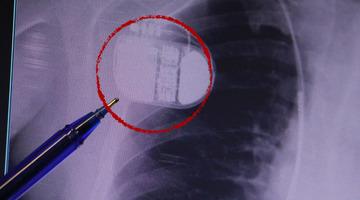

Sporcuların ağız koruyucusundan ilham alınarak üretilen Oniris Horlama Protezi, uyku esnasında alt çenenizi önde tutarak havanın gırtlaktan rahatça geçmesini sağlar. Horlama ve uyku apnesini ortadan kaldırdığı klinik olarak onaylanmış olan bu protez, her kullanıcının ağız yapısına da uyum sağlayabilecek şekilde tasarlandı.